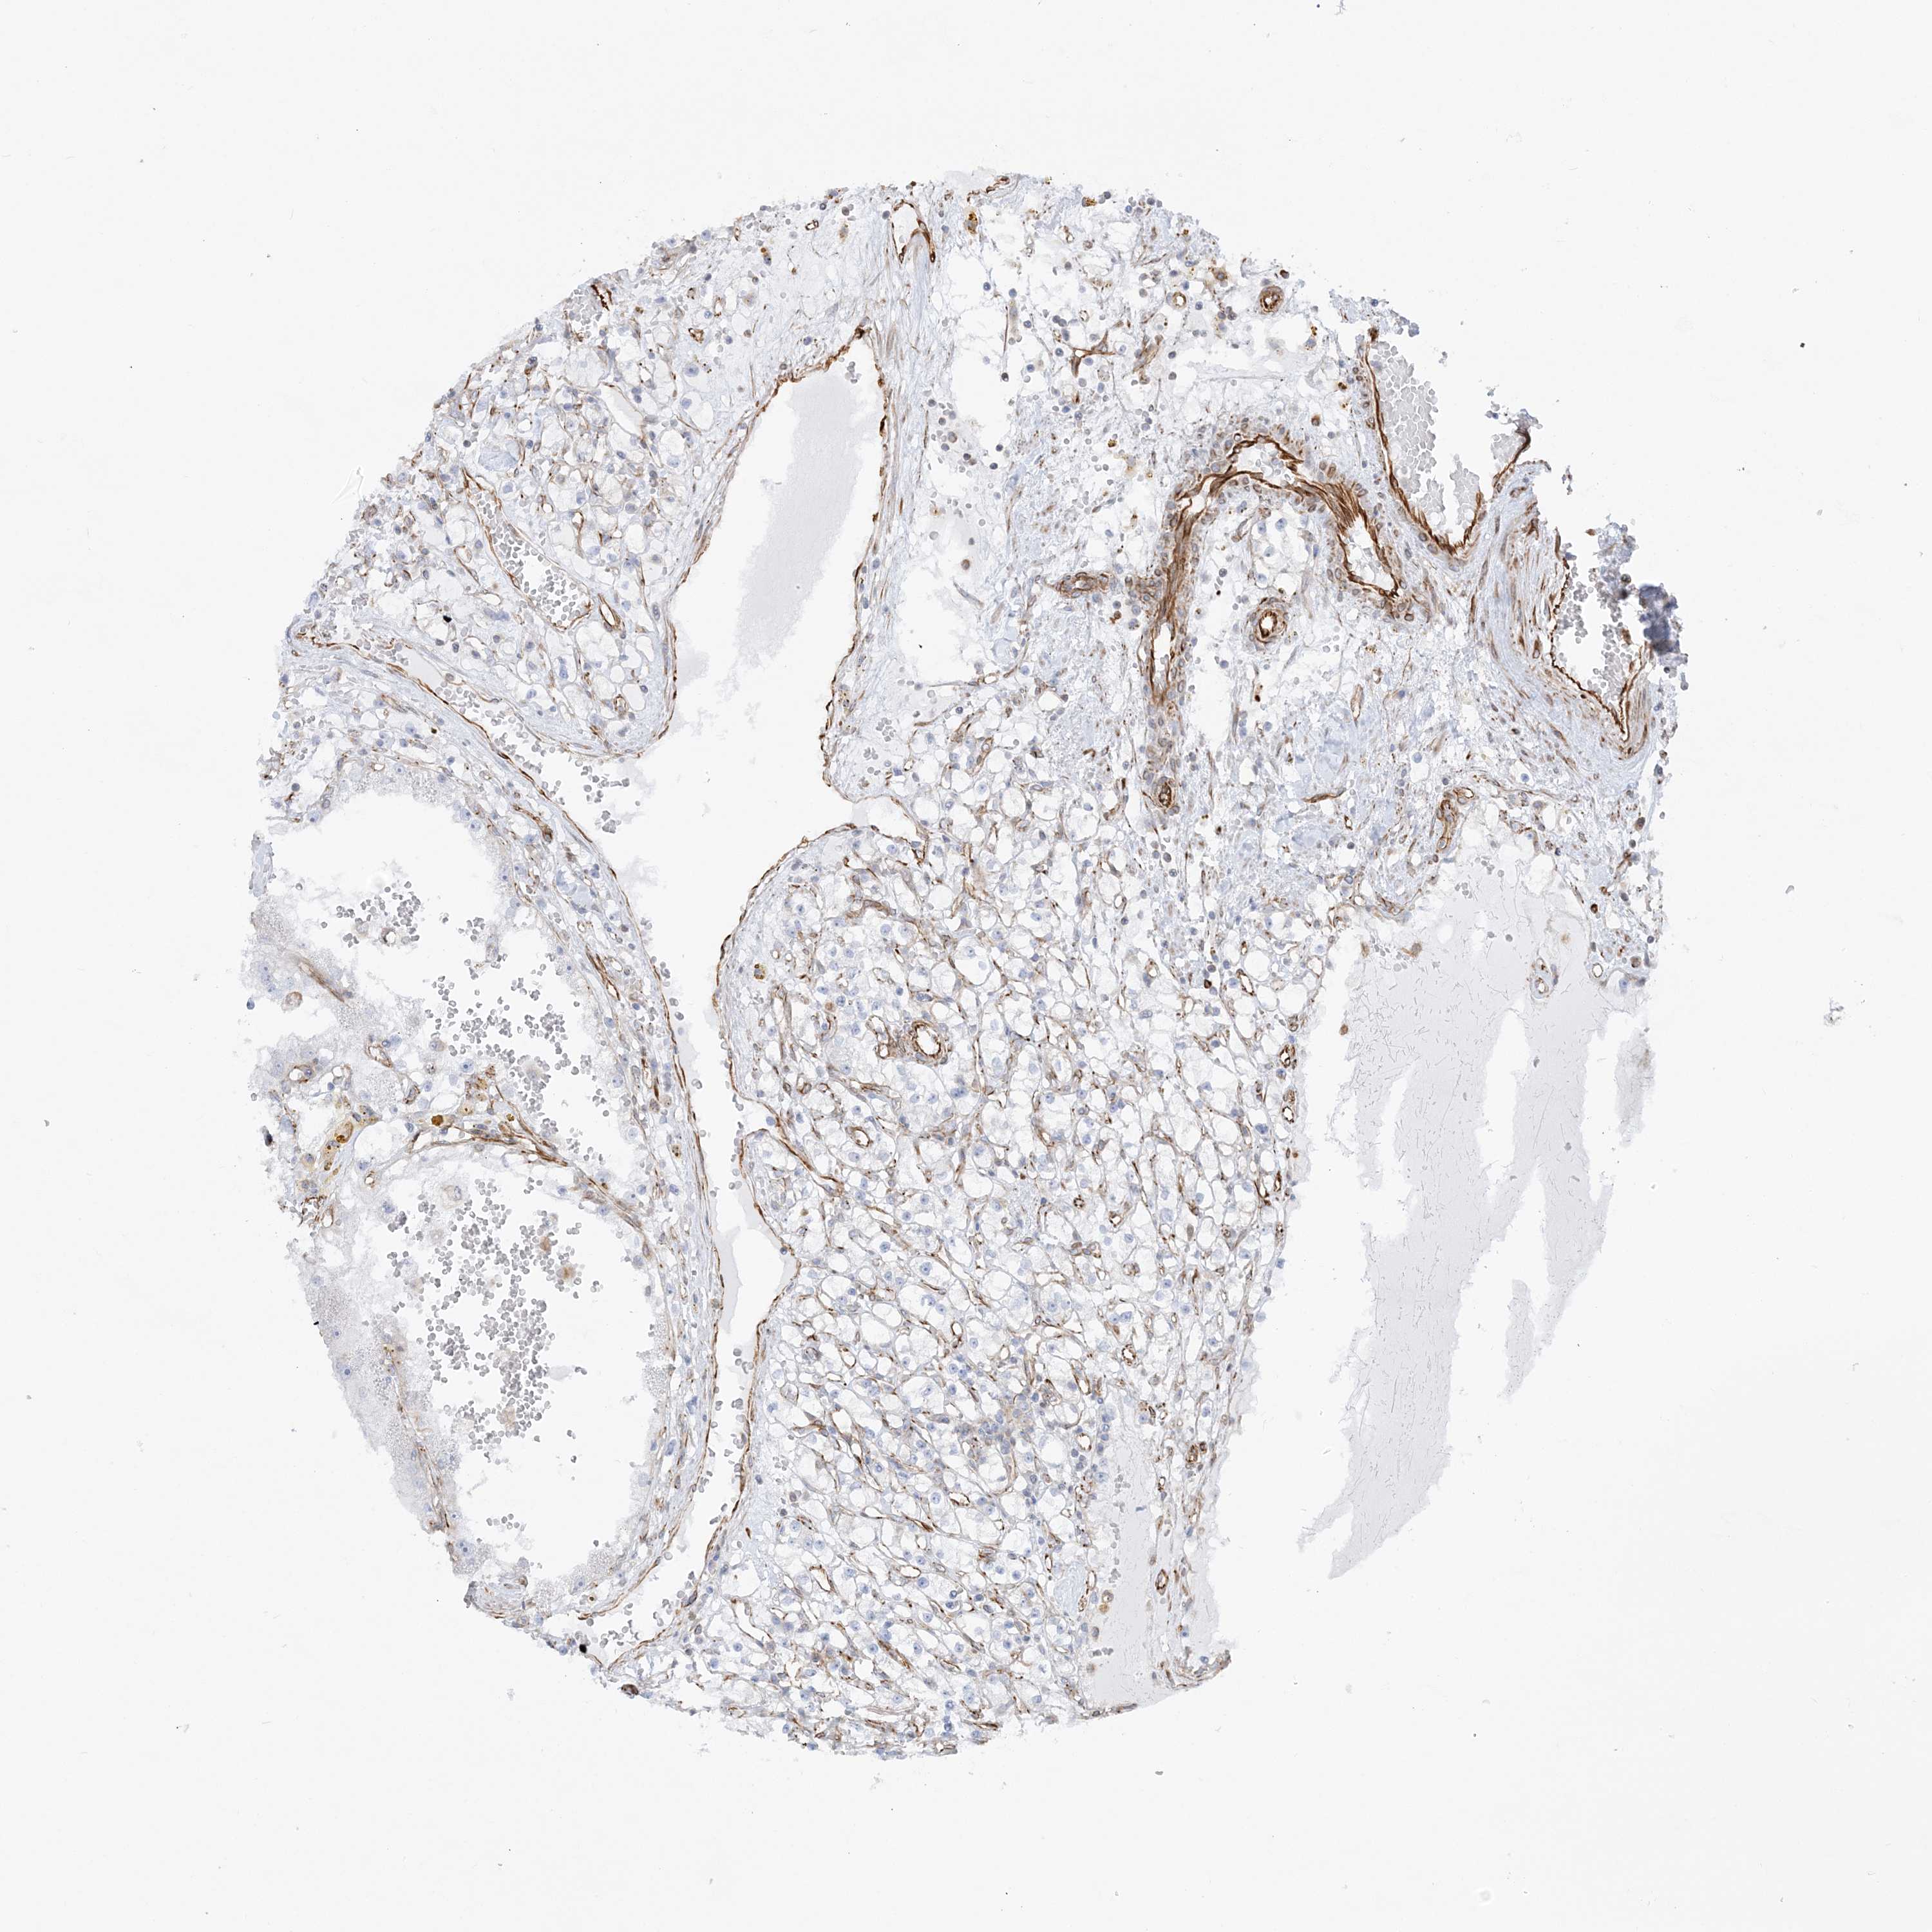

CANCER RENAL CANCER Show tissue menu

KICH TCGA KIRC TCGA KIRC VALIDATION KIRP TCGA PROTEIN RCC CPTAC PROTEIN EXPRESSION

KIDNEY CHROMOPHOBE (TCGA) - Interactive survival scatter ploti

The Survival Scatter plot shows the clinical status (i.e. dead or alive) for all individuals in the patient cohort, based on the same data that underlies the corresponding Kaplan-Meier plots. Patients that are alive at last time for follow-up are shown in blue and patients who have died during the study are shown in red.

The x-axis shows the expression levels (FPKM) of the investigated gene in the tumor tissue at the time of diagnosis. The y-axis shows the follow-up time after diagnosis (years). Both axes are complimented with kernel density curves demonstrating the data density over the axes. The top density plot shows the expression levels (FPKM) distribution among dead (red) and alive patients (blue). The right density plot shows the data density of the survived years of dead patients with high and low expression levels respectively, stratified using the cutoff indicated by the vertical dashed line through the Survival Scatter plot. This cutoff is automatically defined based on the FPKM cutoff that minimizes the p-score. The cutoff can be changed by dragging the vertical line or by entering a cutoff value in the square labeled "Current cut-off".

Under the Survival Scatter plot the p-score landscape (black curve; left axis) is shown together with dead median separation (red curve; right axis). Dead median separation is the difference in median mRNA expression between patients who have died with high and low expression, respectively. It is calculated as follows: median FPKM expression of dead patients with high expression - median FPKM expression of dead patients with low expression. This is intended to aid the user in visually exploring custom cutoffs and the associated p-scores and dead median separation.

Individual patient data is displayed and can be filtered by clicking on one or more of the category buttons on the top of the page. Categories describing expression level and patient information include: high, low, alive, dead, female, male and tumor stages. The scale of the x-axis can be toggled between linear and log-scale by clicking on the "x log" button. Mouse-over function shows TCGA ID, patient information and mRNA expression (FPKM) for each patient.

& Survival analysisi

Kaplan-Meier plots summarize results from analysis of correlation between mRNA expression level and patient survival. Patients were divided based on level of expression into one of the two groups "low" (under cut off) or "high" (over cut off). X-axis shows time for survival (years) and y-axis shows the probability of survival, where 1.0 corresponds to 100 percent.

SCLT1 is not prognostic in Kidney Chromophobe (TCGA)